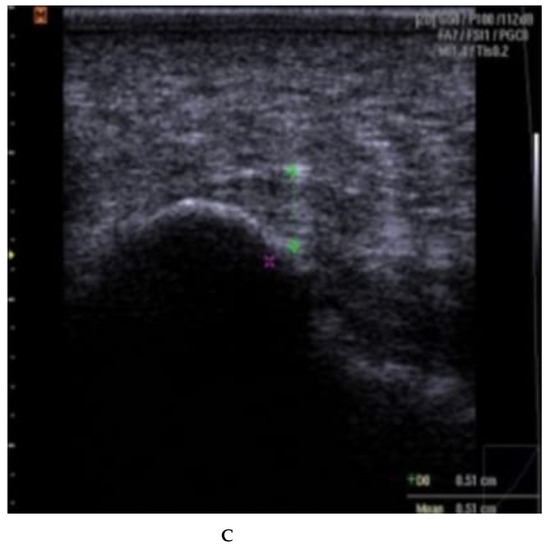

Fascia thickness and echogenicity. All patients had an increased plantar fascia thickness (3.50–8.0 mm) at baseline when measured with MSKUS, and all had hypo-echogenicity. There was a significant difference in the reduction of the plantar fascia thickness between the two groups at 4 weeks follow-up in favor of CSI + TUS (p = 0.004, Table 5), as also shown in Figure A1 and demonstrated in ultrasound images in Figure A2 and Figure A3. At the 12-week follow-up, plantar fascia thickness was significantly higher in the CSI + TUS group (p = 0.012), with an insignificant difference in the decrease between both groups (p = 0.216).

Echogenicity change (Figure A2 and Figure A3) from hypoechoic to iso- or hyperechoic was statistically significant in both groups at 12-week follow-up, but no significant difference was found between the groups (p = 0.208; Table A1).

(A–C): plantar fascia thickness and echogenicity before, after 4 weeks, and 12 weeks follow-up (ESWT). (A). Plantar fascia thickness (0.53 cm) and echogenicity (hypoechoic) before ESWT; Ankles are in 90 dorsiflexion;. Images obtained just medial to the midline, at the proximal end of the plantar fascia, distal to its origin, from the medial tubercle of the calcaneus; Thickness of the plantar fascia was measured from the base of the medial calcaneal tubercle, where a bright echogenic line was easily visible. (B). Plantar fascia thickness (0.51 cm) and echogenicity (hypoechoic) after 4 weeks. (C). Plantar fascia thickness (0.48 cm) and echogenicity (hypo-echoic) after 12 weeks.